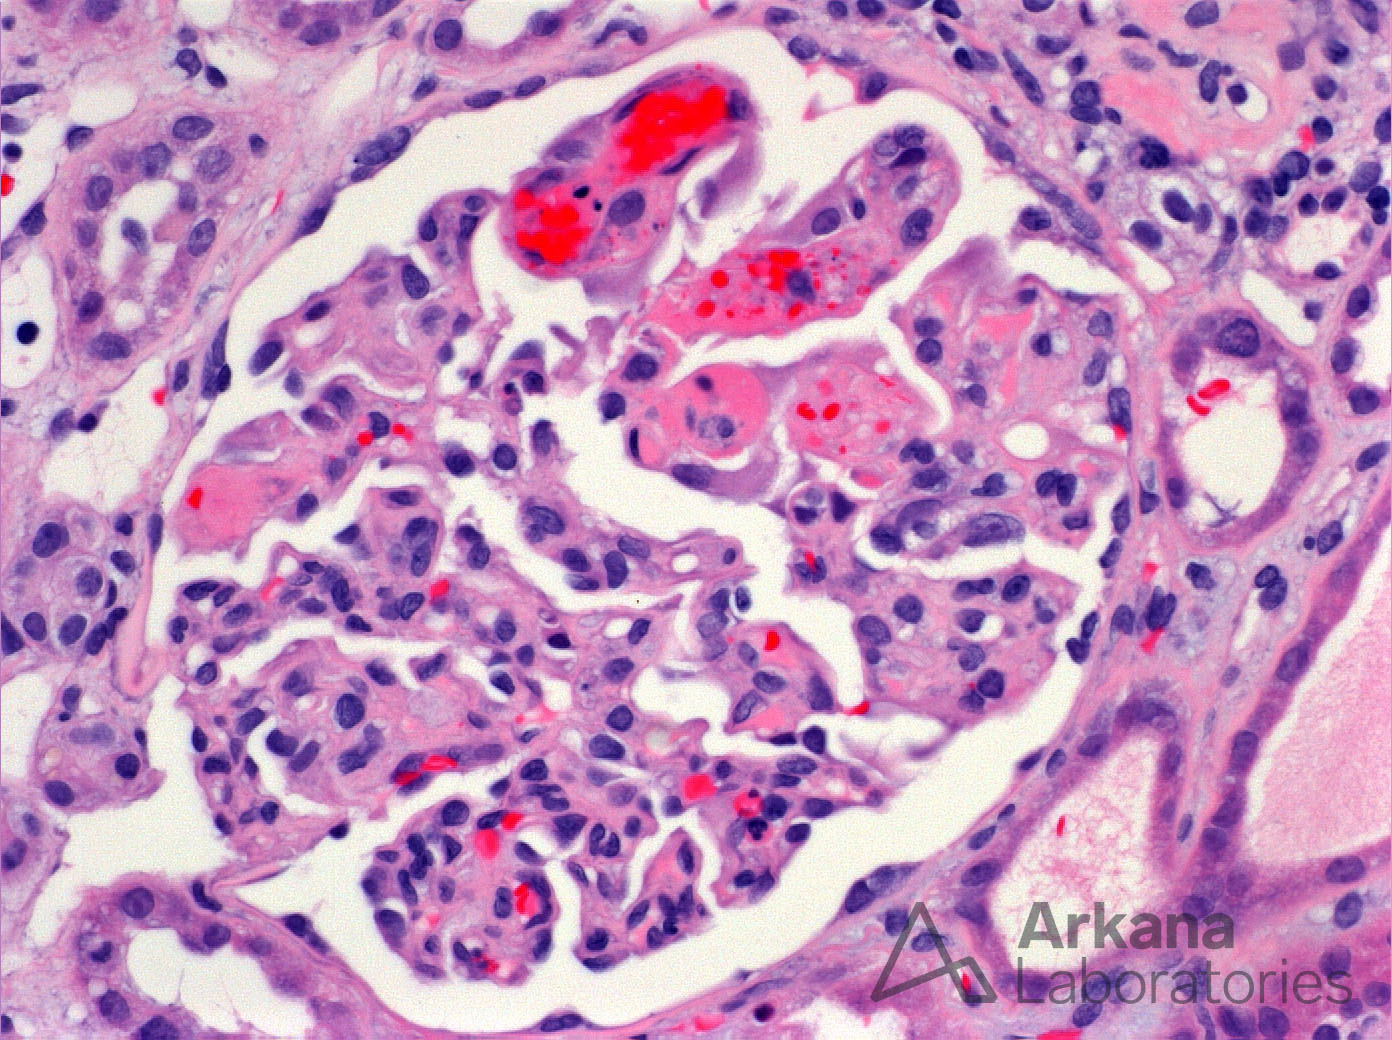

RBC Fragments, Mesangiolysis and Fibrin Thrombi in TMA